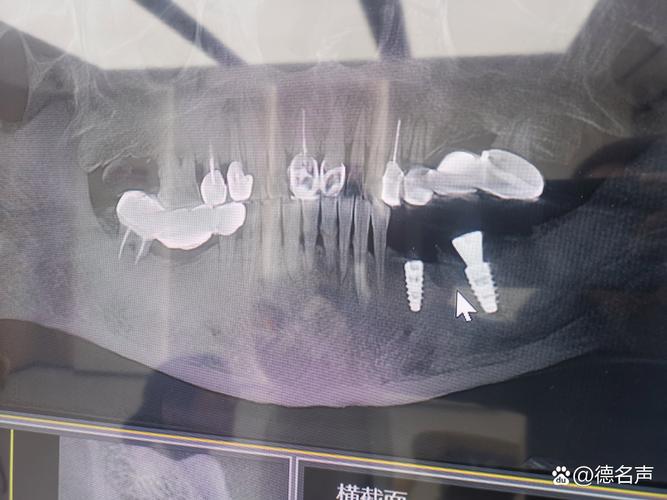

骨量不足: 上颌窦底壁下方是种植体需要扎根的牙槽骨,如果缺牙时间较长,牙槽骨会吸收变薄,当骨高度不足以完全包裹种植体(通常需要至少5-8mm高度,具体视种植体系统而定)时,直接种植就有风险:

- 种植体穿入上颌窦: 种植体尖端可能穿透上颌窦底壁,进入窦腔,这会导致感染、疼痛、种植体松动、失败等严重后果。

- 初期稳定性差: 骨量不足会导致种植体植入后初期不够稳固,影响骨结合(种植体与骨头长牢)的成功率。

上颌窦炎风险: 上颌窦本身有炎症或易感体质的患者,种植体靠近或穿入窦腔会大大增加感染和诱发/加重上颌窦炎的风险。

- 务必进行CBCT检查: 这是评估上颌窦位置、骨高度、骨质量的金标准,没有CBCT,无法准确判断“近”到什么程度,以及是否需要提升。